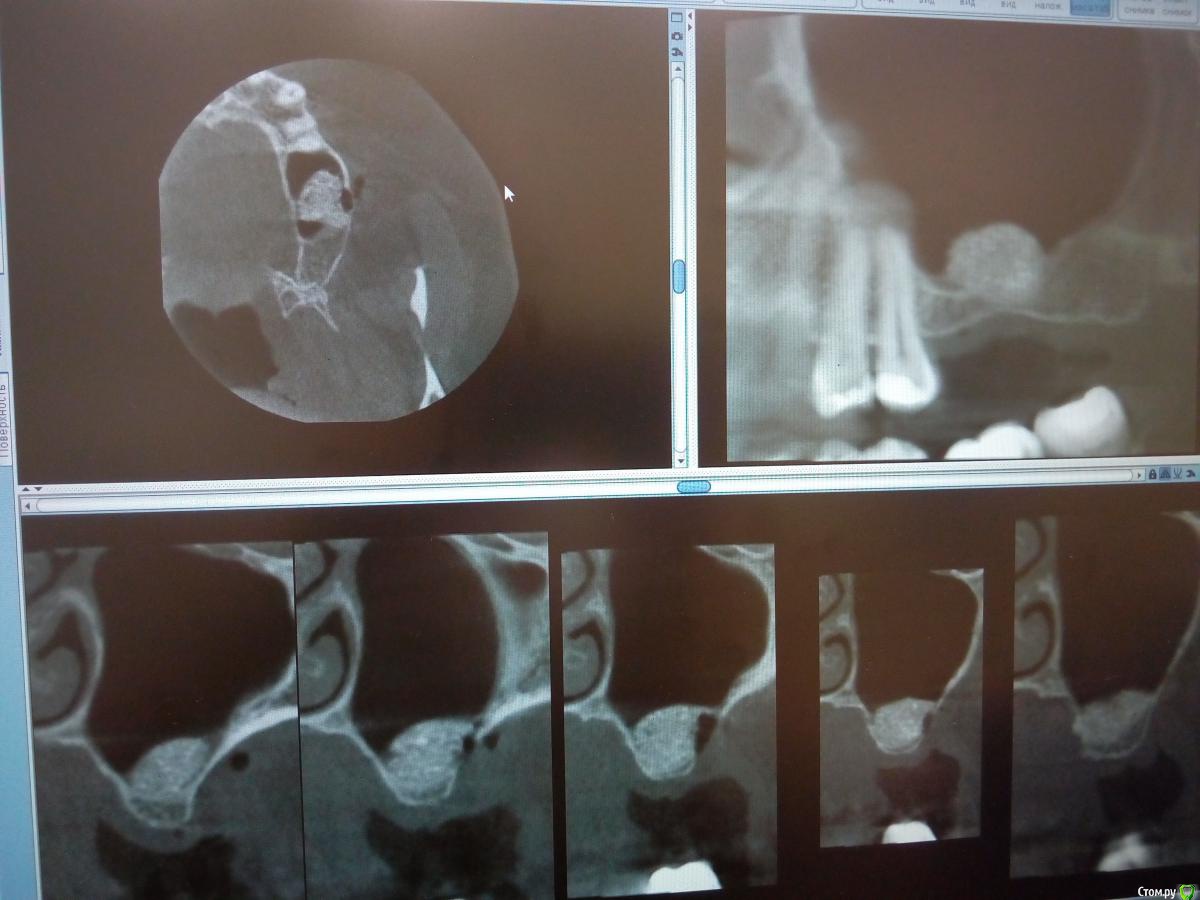

kamranchick Опубликовано 30 января, 2018 Поделиться Опубликовано 30 января, 2018 Господа приветствую, а можно ли как то оценить операцию синуса до сверления?Хорошо был произведен или нет? сделал с 2 сторон , но во 2 сегменте какая то странная ситуация.повторное кт через 6 месяцев. Ссылка на комментарий

red_butler Опубликовано 31 января, 2018 Поделиться Опубликовано 31 января, 2018 С обеих сторон странно выглядит Ссылка на комментарий

Борис80 Опубликовано 2 февраля, 2018 Поделиться Опубликовано 2 февраля, 2018 слева , видимо, десна вросла в окно, я бы предположил...На вскидку скажу, что на каждую пазуху минимум 2 грамма планирую, тем более когда там только кортикалка, Вы плотно "пакуете" материал ? Я бы сверлился и смотрел плотность Ссылка на комментарий

kamranchick Опубликовано 2 февраля, 2018 Поделиться Опубликовано 2 февраля, 2018 слева , видимо, десна вросла в окно, я бы предположил...На вскидку скажу, что на каждую пазуху минимум 2 грамма планирую, тем более когда там только кортикалка, Вы плотно "пакуете" материал ? Я бы сверлился и смотрел плотность торк 40 на каждой стороне, все хорошо получилось, но в 2 сегменте какая то кость непонятная вот как определять без сверления че и как, нигде и не описано Ссылка на комментарий